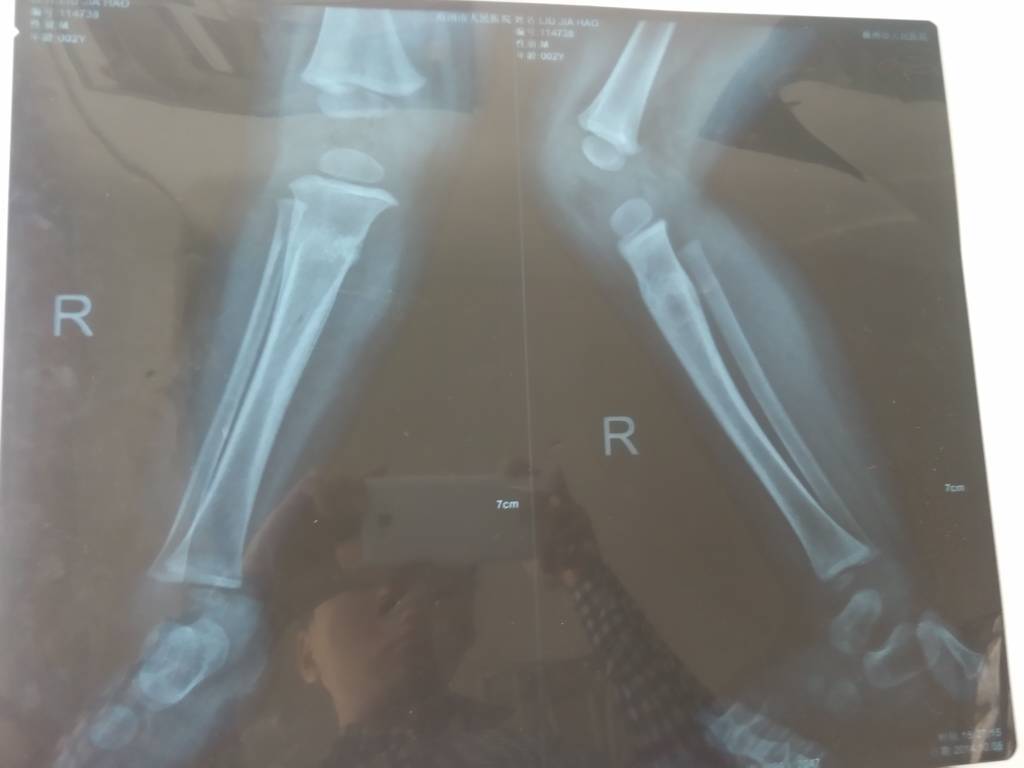

两岁小孩摔伤骨折已经有三个多月了,走路还是不正常,医院说拍片骨头正常 这该怎么办? 点击展开 匿名用户 2014-11-10 15:05 为您推荐: 其他回答 您好,一般骨折的处理都是固定,保养,服用促进骨质生长的药物。 一定要及时处理骨折,避免骨头的断端刺伤体内的其他组织,引发不必要的感染。希望我的答复能帮组到你,祝您早日康复! 张丽医师 2014-11-11 13:50 相关问题 五岁小孩摔了一跤,大腿痛,走路一拐一拐的 带他去医院拍片,诊断说:右股骨头骨折(线形) 请问严重不 未满月的小孩锁骨摔伤、骨折怎么办?怎么调养? 2014年3月26号,14岁小孩摔伤,造成右股骨头骨折